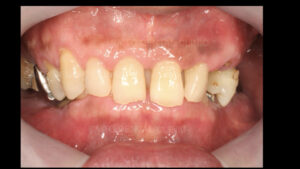

60代の男性の患者様ですが噛めないので歯を入れたいとのことで来院されました

一見すると歯がたくさんあるのでうまく噛めそうですがお口を審査していくと

噛み合っている歯がほとんどなく今まで保険治療で入れ歯や差し歯をしてきたが

歯が壊れるのが止まらないとのことでした

お口の中を見せていただくと左上の奥歯と右下の奥歯が失われています

そして前歯がうまく噛み合っていないので実質噛める歯がほとんどなく

奥歯が壊れるに従って噛み合わせの高さも失われて下の前歯が上の顎に刺さってしまうような状態です